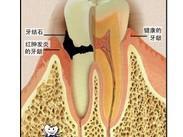

智齒冠周炎

628健康網(wǎng)為您分享有關(guān)智齒冠周炎的癥狀,智齒冠周炎的治療方法,智齒冠周炎的預(yù)防知識(shí),智齒冠周炎的癥狀圖片,智齒冠周炎...

牙癰

628健康網(wǎng)為您分享有關(guān)牙癰的癥狀,牙癰的治療方法,牙癰的預(yù)防知識(shí),牙癰的癥狀圖片,牙癰吃什么藥,牙癰怎么治療,牙癰患者食...

牙源性皮瘺

628健康網(wǎng)為您分享有關(guān)牙源性皮瘺的癥狀,牙源性皮瘺的治療方法,牙源性皮瘺的預(yù)防知識(shí),牙源性皮瘺的癥狀圖片,牙源性皮瘺...